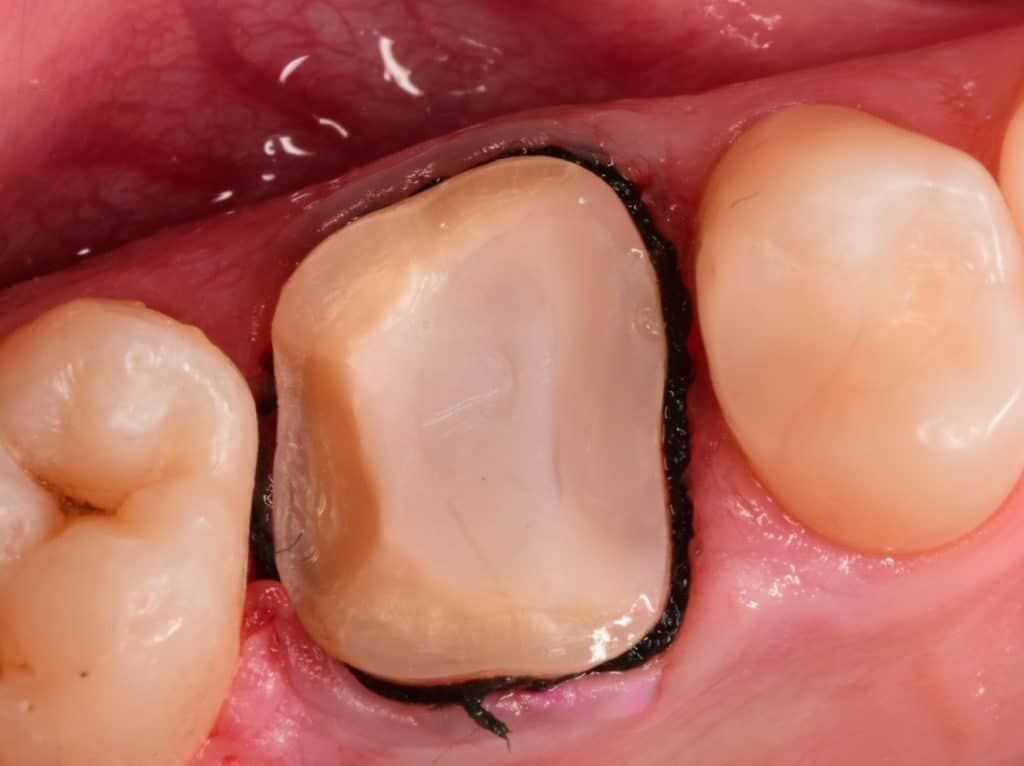

-Isolation with a rubber dam

Isolation with rubberdam

Cementation day

Cementation with heated composite